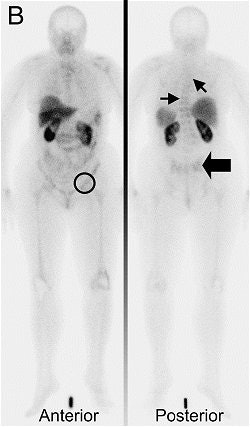

![]() |

| Tc-99m depreotide scintigraphy, assessed before switch to second-line hormonal therapy, was negative. She was a nonresponder and the number of bone lesions increased. Bieke Van Den Bossche, Simon Van Belle, Frederic De Winter, Alberto Signore, and Christophe Van de Wiele. "Early Prediction of Endocrine Therapy Effect in Advanced Breast Cancer Patients Using 99m-Tc-Depreotide Scintigraphy" J Nucl Med 2006; 47;6-13, Figure 3. |